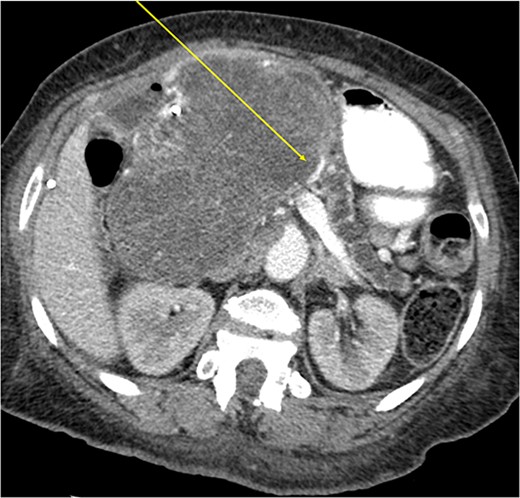

Another abdominal CT was performed redemonstrating the large heterogenous mixed attenuating mass within the right abdomen measuring 14.0 × 10.0 × 13.0 cm likely originating from the pancreatic head with resultant displacement of the PTC anteriorly and to the right with extensive pancreatic ductal dilation (Figs 2 and 3).

Mass effect to abdominal viscera from the 14 × 10 × 13 cm pancreatic head mass.

The mass extended up into the base of the liver, effaced the portal and superior mesenteric veins (SMV) (Fig. 4), and displaced the hepatic and superior mesenteric arteries.